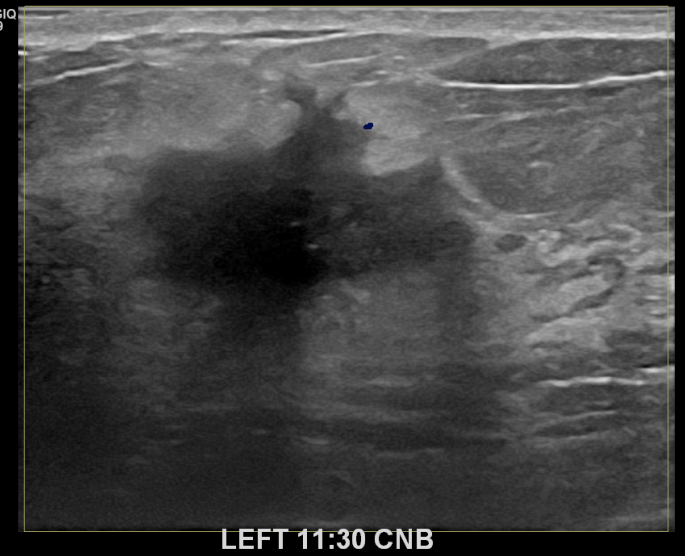

상기환자 좌측 멍울과 통증으로 내원하신 40대중반 여성분으로 의심스러운

좌측혹 조직검사 시행해 침윤성암으로 진단되었습니다